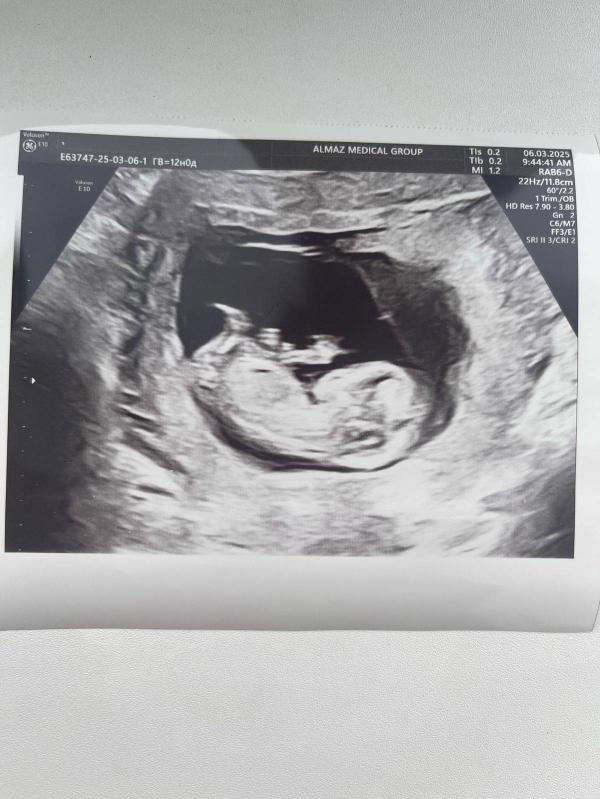

Первое фото УЗИ! Нам 12 недель, как быстро летит время! Все ли хорошо у малыша?

Наше первое фото) мой сын нам ровно 12 недель все хорошо